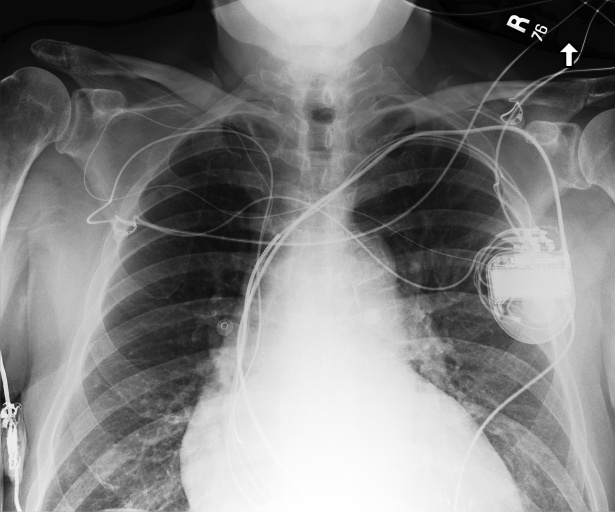

Figure 3 shows phrase grounding results for the phrase “Chronic inflammatory changes predominantly in both lung apices” on an image from PadChest-GR [11]. Both CURE and MAIRA-2 successfully identify the lung apices associated with the described findings. However, CURE’s localization is more accurate and better aligned with the phrase semantics, while MAIRA-2 provides a coarser prediction that only partially covers the relevant areas. As expected, MedGemma-4B-IT does not produce visual grounding outputs, and thus no bounding boxes are shown for this model.